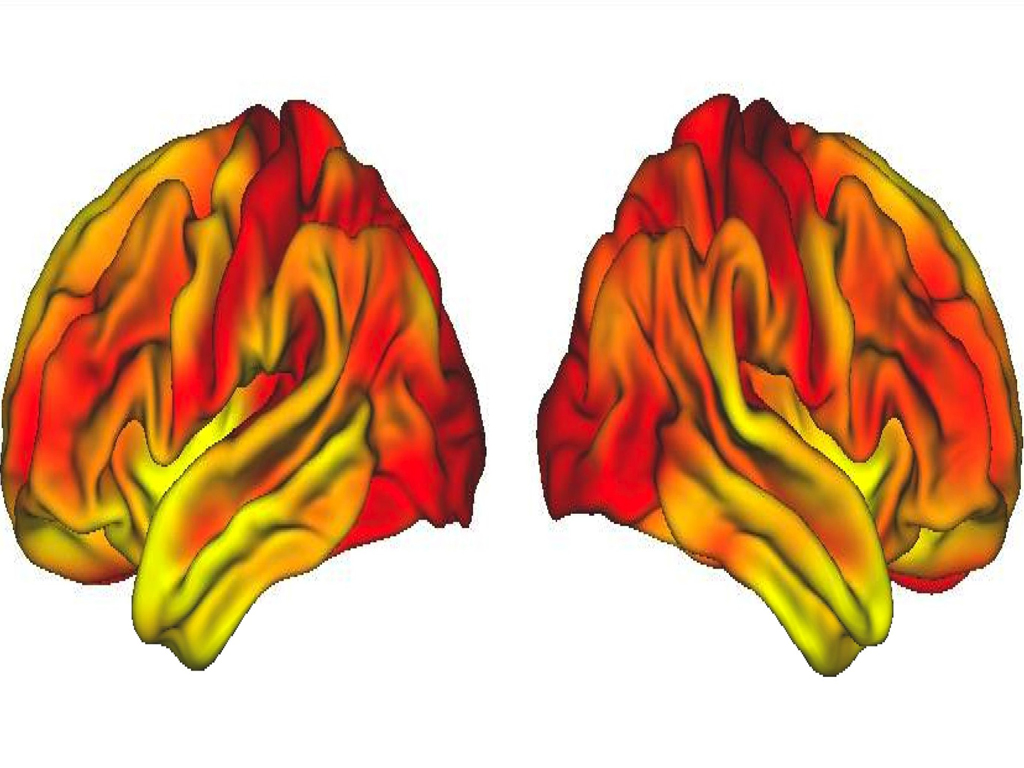

Μια νέα αμερικανική επιστημονική έρευνα για πρώτη φορά βρήκε ότι ακόμη και στη μέση ηλικία ο εγκέφαλος των πλουσιότερων εμφανίζει διαφορές από τον εγκέφαλο των φτωχότερων, όσον αφορά τόσο τον όγκο της φαιάς ουσίας, όσο και την οργάνωση των δικτύων του εγκεφάλου.

Όσοι βρίσκονται ψηλότερα στην εισοδηματική κλίμακα, τείνουν να έχουν περισσότερη φαιά εγκεφαλική ουσία και πιο αποτελεσματική οργάνωση των εγκεφαλικών δικτύων τους, με αποτέλεσμα, μεταξύ άλλων, να διαθέτουν καλύτερη μνήμη και καλύτερη προστασία έναντι της άνοιας στην τρίτη ηλικία, σε σχέση με όσους έχουν χαμηλό κοινωνικοοικονομικό επίπεδο.

Οι ερευνητές συσχέτισαν τη δομή και ανατομία του εγκεφάλου με το εισοδηματικό, το μορφωτικό και εν γένει το κοινωνικοοικονομικό επίπεδο καθενός. Διαπιστώθηκε ότι τα άτομα 35 έως 64 ετών που ανήκαν στο υψηλότερο επίπεδο της κλίμακας, είχαν περισσότερη φαιά ουσία και καλύτερη οργάνωση εγκεφαλικών δικτύων. Αντίθετα, οι φτωχότεροι είχαν λεπτότερη φαιά ουσία και λιγότερο οργανωμένα εγκεφαλικά δίκτυα. Αυτό μάλιστα ίσχυε ανεξάρτητα από το αν ένας ενήλικας στην παιδική ηλικία του είχε περάσει άνετη ή φτωχική ζωή.